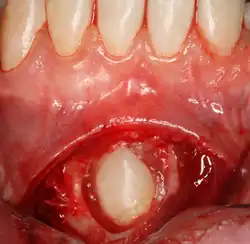

Die Oralchirurgie ist ein Teilgebiet der Zahnmedizin, das „die zahnärztliche Chirurgie einschließlich der Behandlung von Luxationen und Frakturen im Bereich der Zahn-, Mund- und Kieferheilkunde (Kieferbruchbehandlung) sowie die entsprechende Diagnostik“ (Musterweiterbildungsordnung (MWO) der Bundeszahnärztekammer[1], § 14 (2)) umfasst.

- operative Weisheitszahnentfernung

- Entfernung verlagerter Zähne

- Zahnfreilegungen